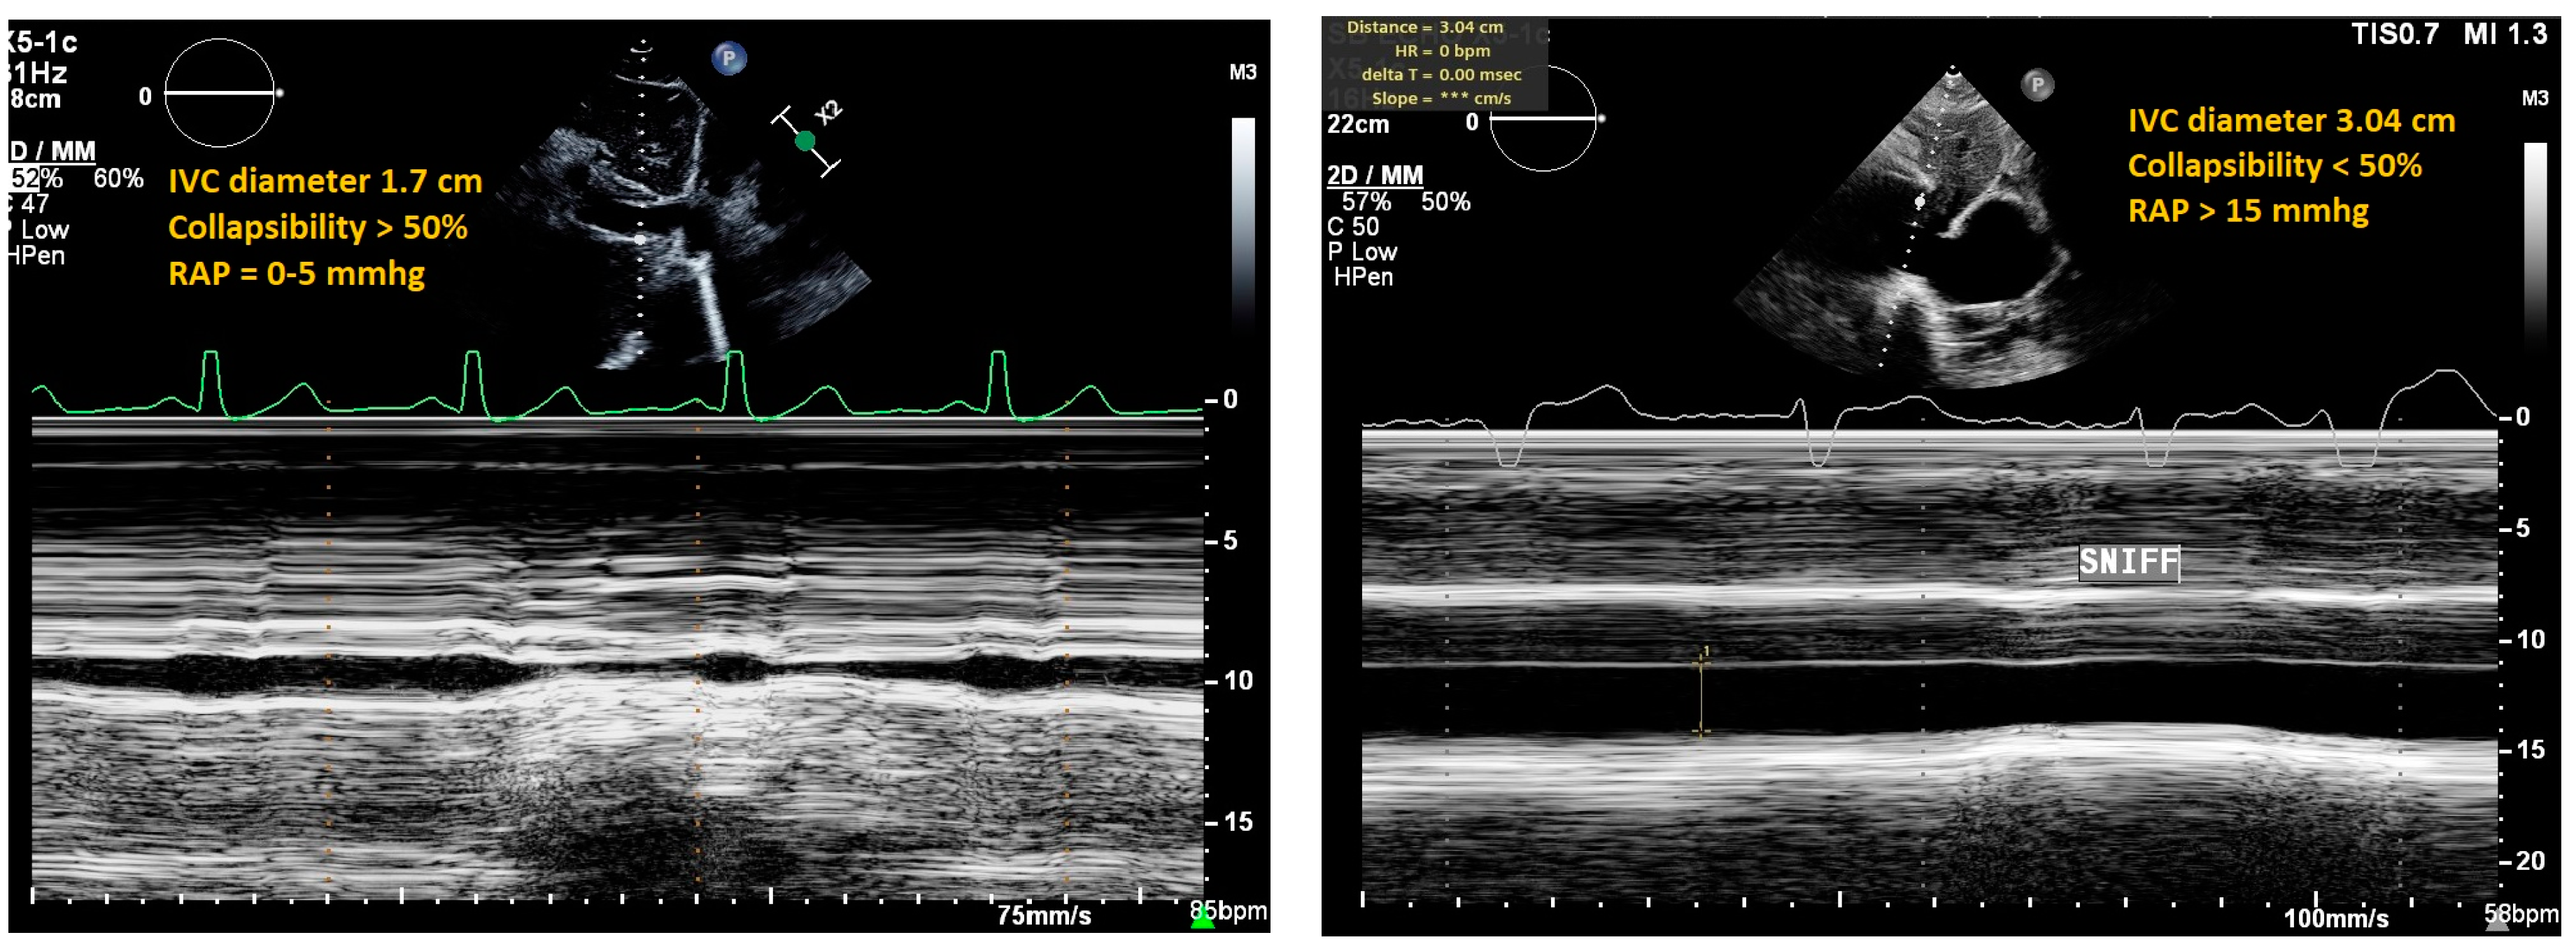

| IVC Ultrasound | ||||

| Inferior vena cava (IVC) diameter and collapsibility with inspiration | Diameter <21 mm that collapses >50% with sniff |

|

| |